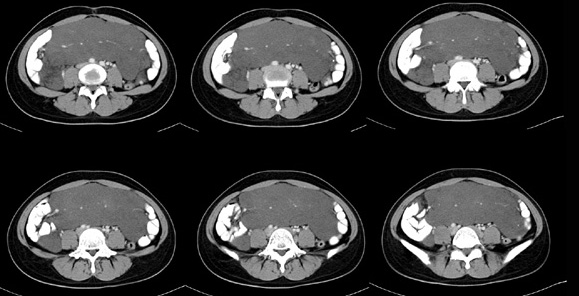

女性,28岁,停经3月,腹部膨隆1月,产前检查发现腹部占位

{肿块中心ct值27hu,增强后,动脉期、门脉期均无明显强化)

患者手术病理:腹腔囊性淋巴管瘤,象这样充满整个腹腔的的确很少见